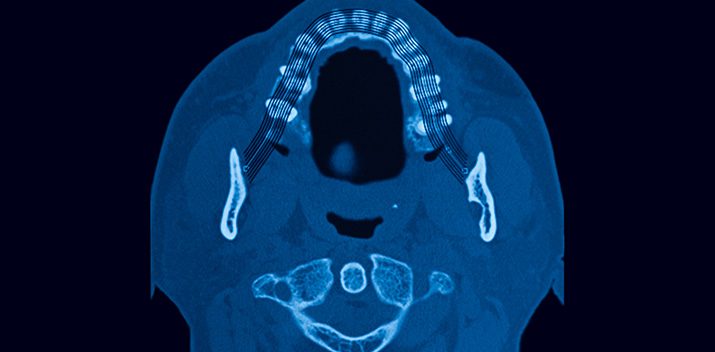

But that’s just the start, digital scans, digital X-Rays and CT scans provide the dentist with far greater quality of information which is more accurate than older traditional methods and allows for faster diagnosis and the treatment of many dental issues.

For cutting edge treatments such as implants it provides a wealth of information to allow specialists to make faster and more informed decisions about the treatments they can offer.